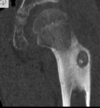

Cisto ósseo aneurismático

Acomete paciente jovem (fise aberta);

Localização excêntrica, aspecto em favo de mel no RX;

Pode ter reforço periosteal;

RM:lesão multicística; Septos + nível liquido-liquido (lesões dx diferencial: COS fraturado, COA, TCG ou osteossarcoma telangiectásico).

Primário ou Secundário à outros tumores: TCG, DF, Condroblastoma.